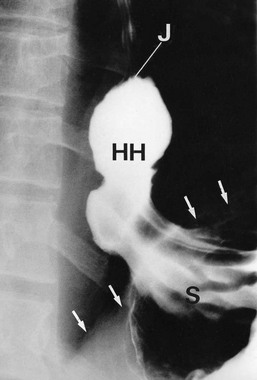

Hiatus hernia occurs when the proximal part of the stomach passes through the diaphragmatic hiatus up into the chest (see Fig. 22.5). Around 90% of hiatus hernias are of the sliding type, in which the gastro-oesophageal junction is drawn up into the chest and a segment of stomach becomes constricted at the diaphragmatic hiatus. The hernia tends to slide up into the chest with each peristaltic contraction. These hernias may become huge and, rarely, may contain the whole stomach including pylorus and first part of the duodenum, sometimes with part of the colon as well. In the 10% of non-sliding cases, the gastro-oesophageal junction remains below the diaphragm and a bulge of stomach herniates through the hiatus beside the oesophagus. These are described as para-oesophageal or rolling hiatus hernias.

Fig. 22.5 Types of hiatus hernia

(a) Sliding hiatus hernia, which is common. This type disrupts the physiological anti-reflux mechanism. (b) Rolling or para-oesophageal hiatus hernia, which is rare. The anti-reflux mechanism is usually left intact

In sliding hiatus hernia, the lower oesophageal sphincter mechanism often becomes defective, causing reflux of acid–peptic stomach contents. This is not a problem with rolling hiatus hernias which more usually present with pain or dysphagia.

In general, hiatus hernias are assessed at endoscopy, with biopsy if necessary. The latter is important to exclude carcinoma, especially in dysphagia. In specialised units, oesophageal manometry studies can assess the oesophageal muscular function and oesophageal pH studies assess the extent and severity of reflux. These studies help determine which patients are likely to benefit from surgery. Rarely barium swallow examination (see Figs 22.6 and 22.7) may be necessary to delineate complicated anatomy.